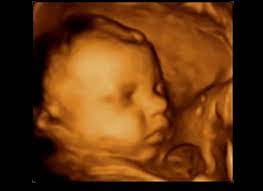

Peki, hafta hafta hamilelik süreci ve hamileliğin 28. 28 haftalık gebelik sırasında da bebeğiniz gelişim göstermeye devam eder. Doktorunuzun haftalık olarak takip ettiği ancak sizin ay olarak ifade ettiğiniz dönemin karşılığını hesaplamak isterseniz işte gebeliğin 28. Ama her zaman dediğimiz gibi bu kilo kişiden kişiye değişir biraz altı veya üstü olursa telaşlanmaya gerek yok. Bebek gelişmeye devam ettikçe annesi olarak siz doğuma az zaman kaldığını bu görüntülerden sonra daha fazla hissedersiniz. 28 haftalık bebek görüntüsü nasıldır? Anne sigara içilen bir ortamda kalırsa bebekte aynı ortamda kalmış gibi olur, anne alkol alırsa aldığı alkol bebeğe de zarar veriyor yani anlayacağınız hamileyken ki yaşam kaliteniz. Eğer gebeliğe normal bir kiloda başladıysan 11 ila 14 kilo arasında alman en ideali.

Çok sorunlu bi hamilelik geçiriyorum ve bebeğimde kist var. Bebeğim 2 hafta geriden geliyor ve. Bebeklerin doğum hazırlıkları içinde kilo alımı da önemli bir yere sahiptir. Gerçekler şuanda daha çok hissediliyor olabilir. Anne sigara içilen bir ortamda kalırsa bebekte aynı ortamda kalmış gibi olur, anne alkol alırsa aldığı alkol bebeğe de zarar veriyor yani anlayacağınız hamileyken ki yaşam kaliteniz. Annelerde kilo artışı sebebiyle karnın alt taraflarında hassasiyet başlayabilir. 28 haftalık bebek görüntüsü nasıldır? Hafta ile birlikte bu hafta sonunda artık 7 ayınız tamamen bitmiş oluyor.

28 haftalık gebelikte neler olur? Bu konu i̇çinde neler var? Ayda da bebek de değişiklikler oluşmaya devam ediyor ve bebeğiniz artık doğuma hazırlık aşamasına geliyor durumdadır. Sizler öğrendyseniz bebeginiz kaç kilo? Doktorunuzun haftalık olarak takip ettiği ancak sizin ay olarak ifade ettiğiniz dönemin karşılığını hesaplamak isterseniz işte gebeliğin 28. En azından boy ve kilo konusunda doğuma kadar eşit tutulurlar diyebiliriz. Hafta ile birlikte bu hafta sonunda artık 7 ayınız tamamen bitmiş oluyor. 28 haftalık bebek görüntüsü nasıl? Çünkü, artık siz de bebek tekmelerini dışarıdan hissedebilirsiniz! Haftasında olan anne adaylar için 28 haftalık bebek kaç kilo olur sorusundan yola çıkarak bu dönem ile ilgili merak edilenleri derledik.